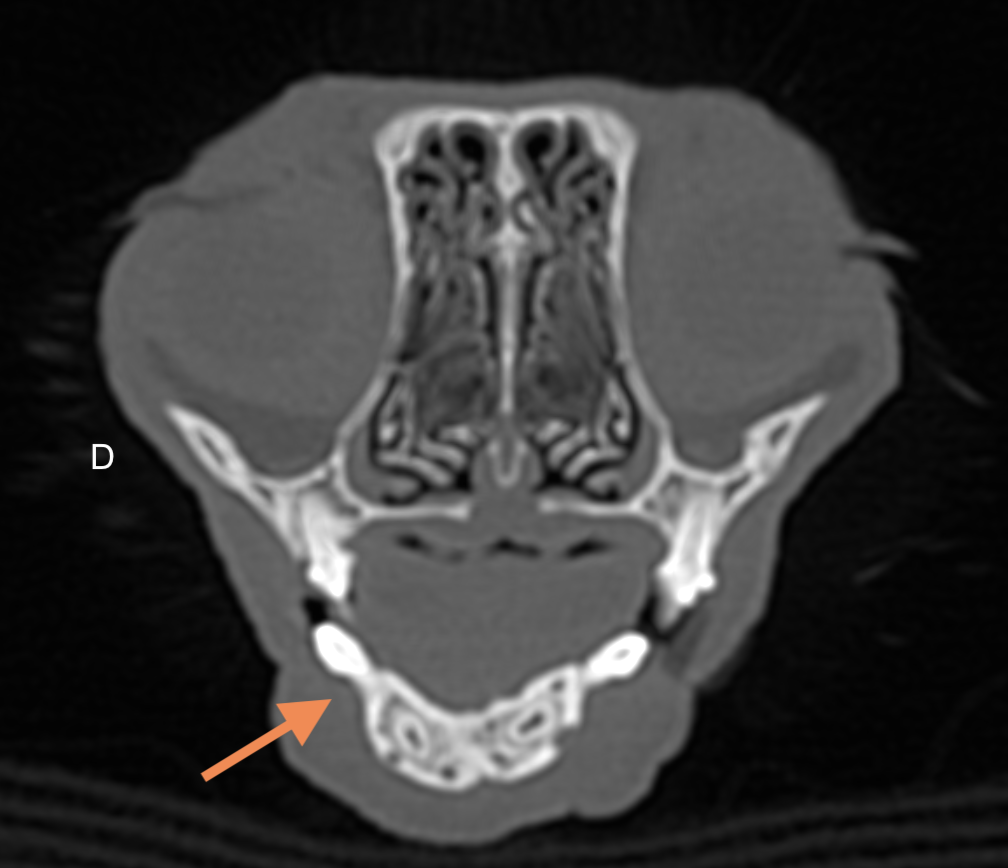

Examens complémentaires

L’examen tomodensitométrique met en évidence une persistance de la fracture articulaire peu déplacée du processus condylaire de la mandibule droite et l’apparition d’une réduction de l’interligne articulaire temporo-mandibulaire évoquant une incongruence articulaire, non visualisée deux mois auparavant. De multiples fractures peu déplacées des structures osseuses de la face et du nez persistent, à l’origine d’une déviation à gauche du massif nasal. Enfin une lésion de fibrose cicatricielle du muscle masséter droit est mise en évidence en regard de l’aire de passage du nerf facial.

Diagnostic

Ankylose unilatérale de l’ATM associée à une paralysie faciale à droite. La cause de la paralysie faciale droite n’est pas certaine, l’hypothèse principale est que la lésion de fibrose cicatricielle du muscle masséter ait pu entraîner une lésion secondaire du nerf facial (inflammatoire ou syndrome des loges par exemple).